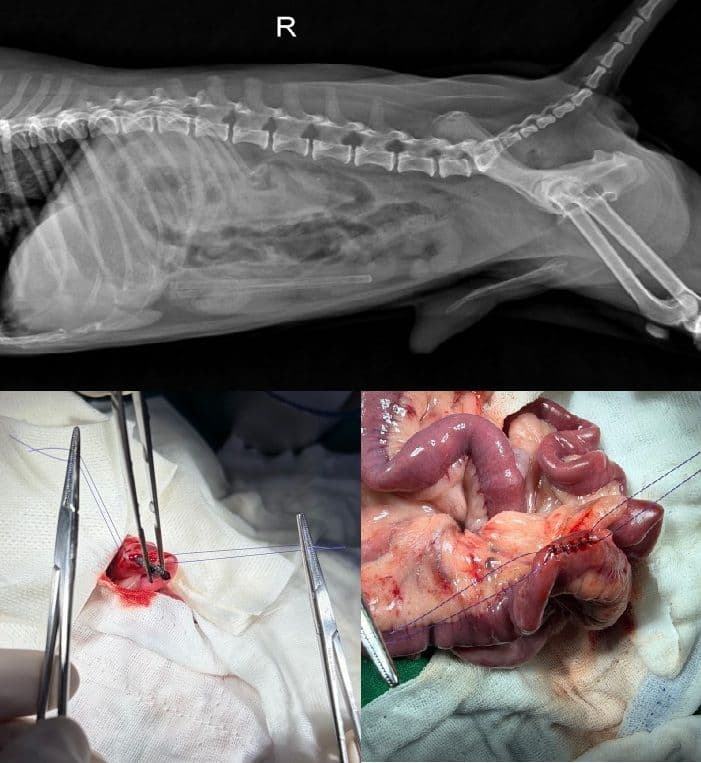

소화기 이물 제거

위/장 내 이물 제거

- 소장 생검